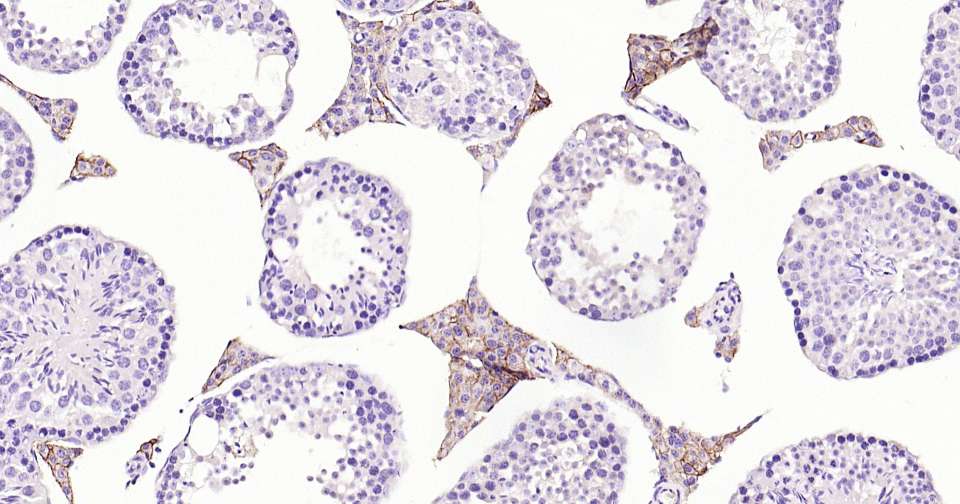

Immunohistochemical analysis of paraffin embedded mouse testis tissue slide using IHC0331M (Mouse CD36 Kit).